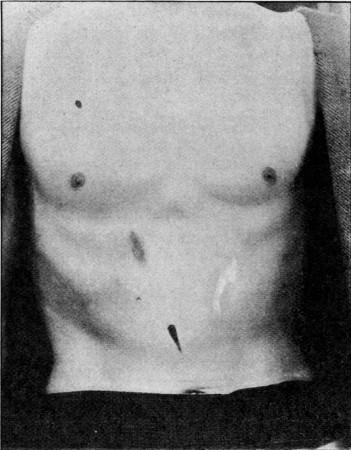

24. Superficial Abdomino-thoracic Track64

25. Superficial Linear Ecchymosis of Thigh65

44. Explosive Wound of Back100

49. Explosive Exit and Entry Wounds of Legs159

50. Types of Gunshot Fracture161

51. Lower End of Fractured Femur164